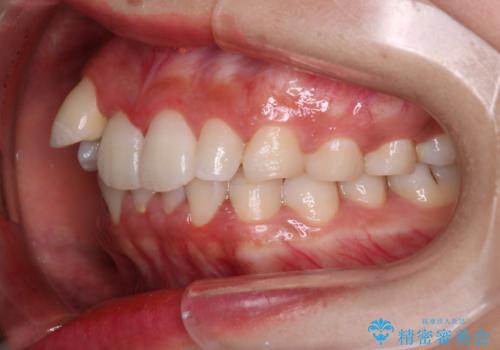

【インビザライン】八重歯が気になる

- 乳歯を抜歯してスペースを確保し八重歯の改善を行いました。

インビザラインをしっかり使用していただいたので、きれいな歯並びになりました。